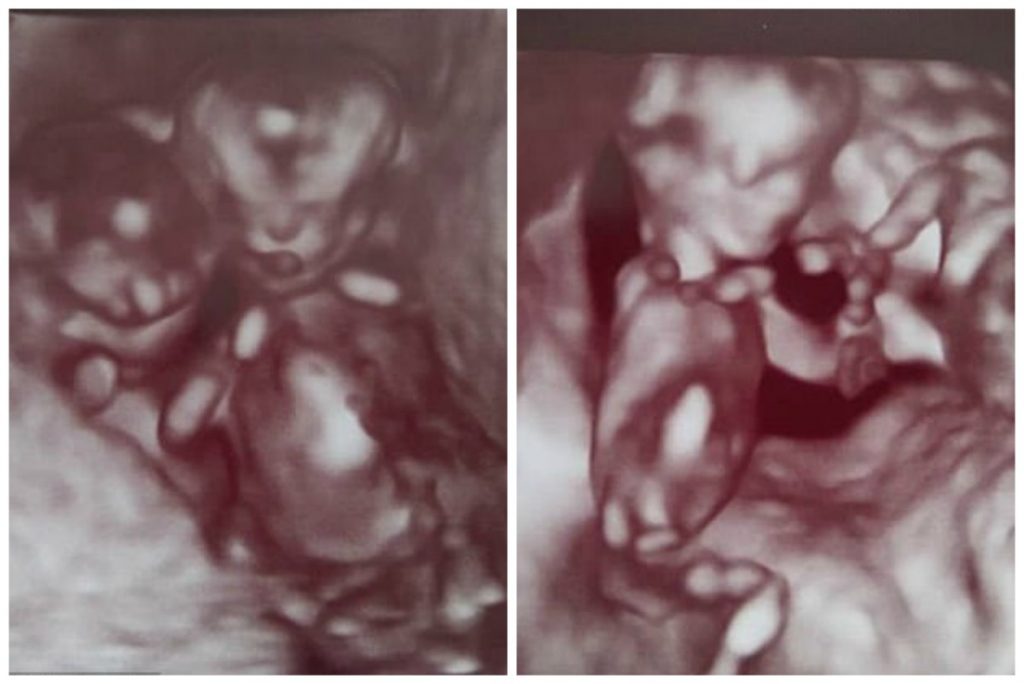

Το υπερηχογράφημα των 10 εβδομάδων έδειξε ότι τα δίδυμα μοιράζονταν τον ίδιο αμνιακό σάκο. Η 30χρονη μητέρα, Vicky Plowright, σοκαρίστηκε όταν έμαθε ότι οι ομφάλιοι λώροι τους θα μπορούσαν να μπερδευτούν μεταξύ τους και να διακόψουν την παροχή οξυγόνου. Αυτό σήμαινε πως θα μπορούσαν να πεθάνουν και τα δύο.

“Το υπερηχογράφημα έδειχνε ότι τα δίδυμα μας μοιράζονταν τον ίδιο αμνιακό σάκο,” συνέχισε η Vicky. “Είπαν ότι σήμαινε ότι τα μωρά ήταν σε υψηλό κίνδυνο και ότι έπρεπε να επιστρέψουμε το συντομότερο δυνατό για να δούμε έναν ειδικό”.

Αλλά τα πάντα άλλαξαν στο υπερηχογράφημα των 12 εβδομάδων, όταν οι γιατροί είπαν στη Vicky και τον Chris πως είδαν ότι τα δίδυμα είχαν μετακινηθεί σε μια στάση που τους έσωσε τη ζωή.

Πανομοιότυπα δίδυμα αγόρια αψήφισαν τις πιθανότητες να στραγγαλίσουν ο ένας στον άλλο στη μήτρα, με αυτή την απίστευτη, ζωηρή αγκαλιά. “Προς έκπληξή μας, κατά το υπερηχογράφημα των 12 εβδομάδων, είδαμε ότι ήταν αγκαλιασμένοι μεταξύ τους και κρατούσαν ο ένας το χέρι του άλλου,” θυμάται η Vicky. “Κρατούσαν ο ένας τον άλλον ζωντανό, παραμένοντας στάσιμοι, κι έτσι οι ομφάλιοι λώροι τους δεν μπερδεύτηκαν.”

Όμως, στο υπερηχογράφημα των 12 εβδομάδων, το ζευγάρι είδε κάτι μαγικό – τα παιδιά τους αγκαλιάζονταν και κρατούσαν ο ένας το χέρι του άλλου. «Με το να κάθονται σε αυτή τη στάση δεν μπερδεύονταν οι ομφάλιοι λώροι τους», είπε η Vicky.